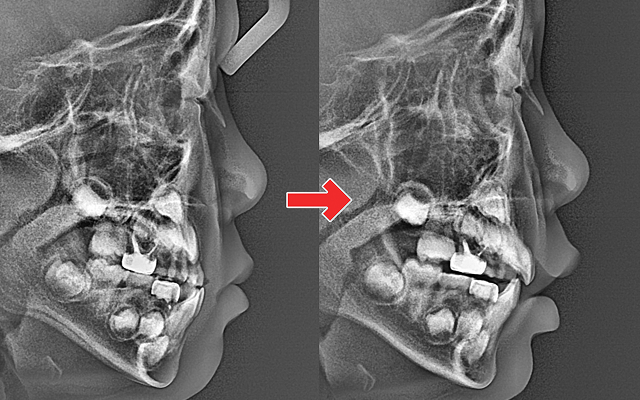

성장기 교정 시기를 놓치면 생길 수 있는 문제

• 01

턱뼈의 성장이 비대칭으로 진행되어 성인 교정 시 수술이 필요할 수도 있음(양악수술)